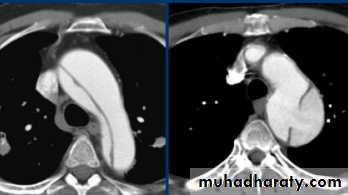

It is important to know the extent of aortic dissections because those involving the ascending aorta are treated surgically, while those confined to the descending aorta are usually treated by an endovascular approach if conservative management is not appropriate.

Aortic dissections can be shown with CT (and MRI) and these non-invasive techniques have, in practice, replaced aortography.

Aortic dissection